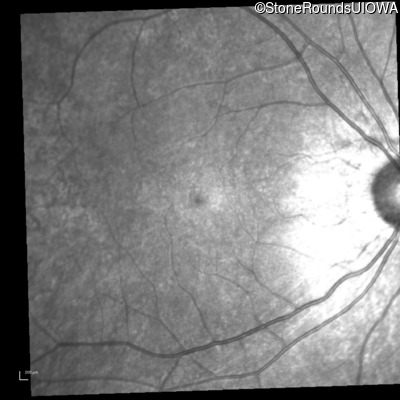

Infrared Fundus Photograph - Right - 20/25 -3

Exemplar

Infrared Fundus Photograph - Left - 20/30 +2